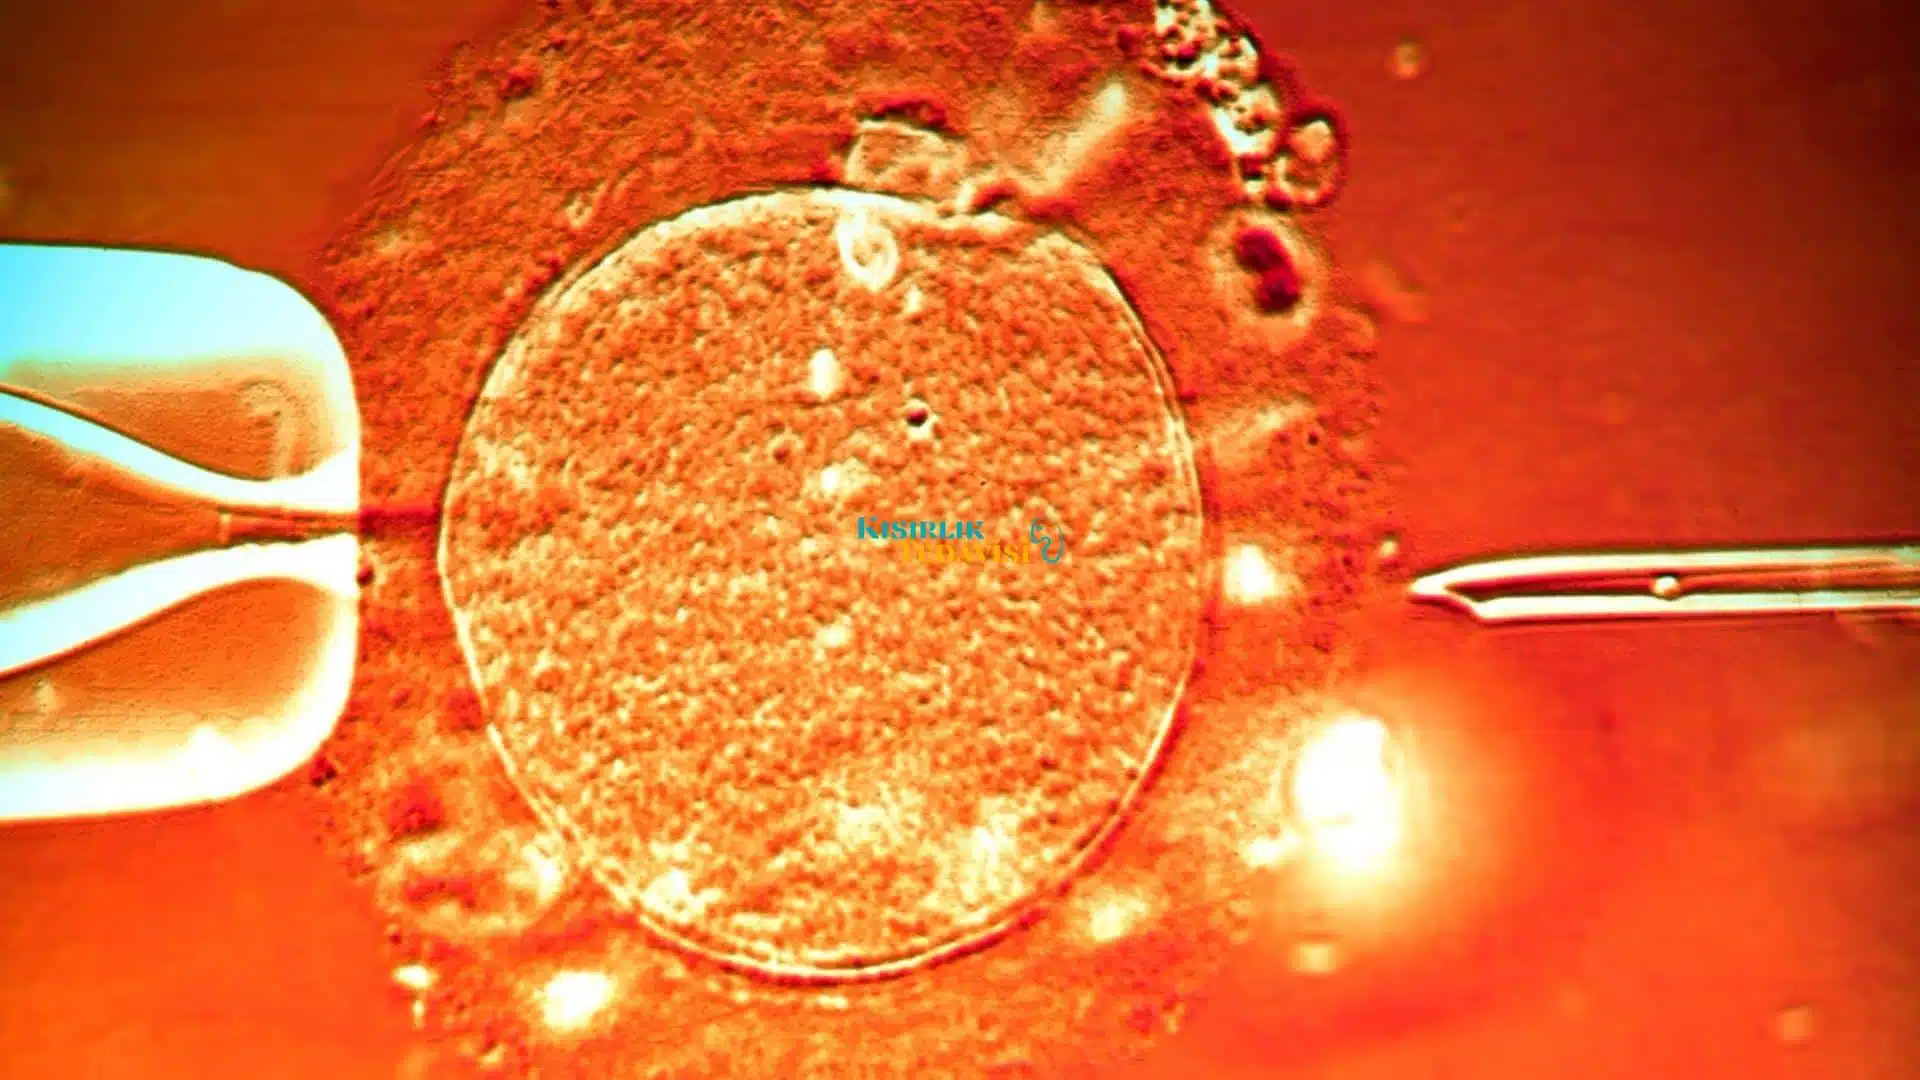

Bu hücreler üzerinde yapılan klinik çalışmalar sonrasında yumurtaya yerleştirme işlemi gerçekleştirilmektedir. Elektrofüzyon ismi verilen yöntem sayesinde, hücrelerden embriyo elde edilmeye çalışılmaktadır. Kısırlıkta rosi yöntemi ile döllenme gebelik oranını belirlemektedir.